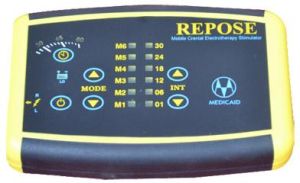

RS Enterprises is one of the noteworthy suppliers of a wide array of highly operational machines. We deal in EMG machine, ECG machine, Neuro Modulation Machine, Digital Biofeedback Machine, Therapy ECT Machine, Transcranial Magnetic Stimulation Machine, Sleep Study Machine, Pulmonary Function Test Machine, Digital Polygraph Machine, Digital Physiograph Machine, Digital Plethysmometer Machine, AD629 Diagnostic Audiometer, AD226 Diagnostic Audiometer, Channel ECG Machine, Electric OT Table and many more. As a respected name in the industry, we procure the entire range of products only from the reliable manufacturers or vendors after checking against numerous quality parameters such as functionality, maintenance, manufacturing defect, etc. We are capable of undertaking bulk as well as urgent orders as we maintain a streamlined inventory management system.